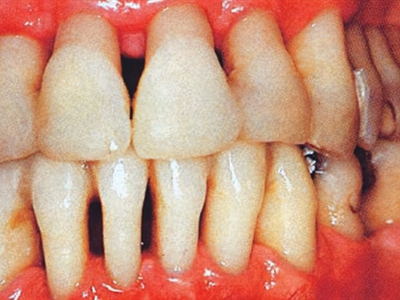

牙龈退缩露出淡黄色牙根图

牙龈退缩患者的牙龈退缩后,淡黄色牙龈明显露出。若进一步发展,易使对应位点的牙槽骨发生骨吸收,可能诱发龋齿、牙龈敏感、菌斑堆积等。